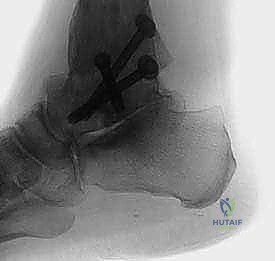

5. التثبيت الميكانيكي (Fixation)

بعد وضع العظام في الزاوية التشريحية الصحيحة تماماً، يتم تثبيتها بقوة لضمان عدم حركتها أثناء فترة الشفاء. يستخدم الدكتور هطيف مسامير ضغط كبيرة من التيتانيوم (Cannulated Screws). يتم إدخال هذه المسامير (عادة مسمارين) عبر عظم الكعب صعوداً إلى عظم الكاحل، وتعمل على ضغط العظمتين معاً بقوة هائلة، مما يوفر بيئة مثالية للاندماج.

6. إغلاق الجرح والجبيرة

بعد التأكد من وضع المسامير بشكل مثالي باستخدام جهاز الأشعة التداخلية (C-arm) داخل غرفة العمليات، يتم إغلاق الشق الجراحي بغرز تجميلية، وتوضع القدم في جبيرة خلفية مبطنة جيداً للحماية.